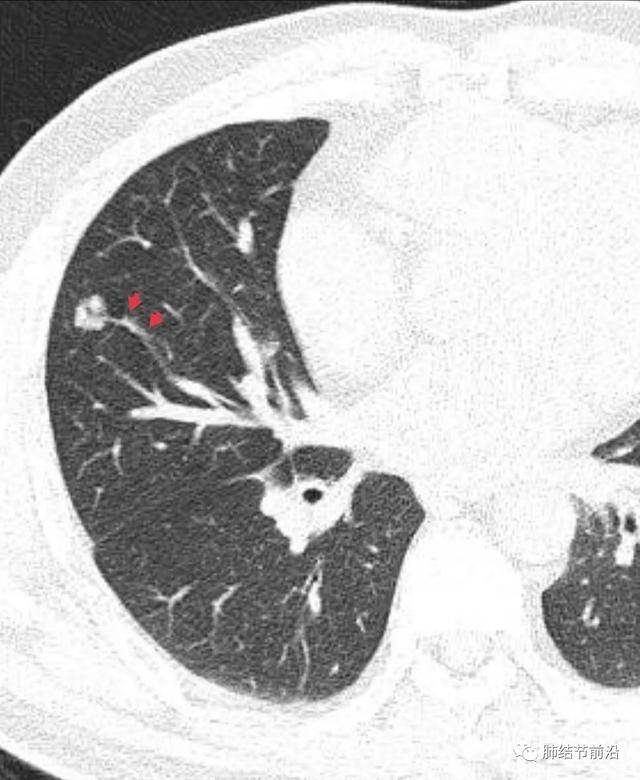

什么是肺結(jié)節(jié)呢?肺結(jié)節(jié)是指肺部出現(xiàn)的一種直徑小于或等于3厘米的圓形或近似圓形的病灶,大多數(shù)肺結(jié)節(jié)是良性的,只有一小部分可能是惡性的。

診斷肺結(jié)節(jié)主要依賴于醫(yī)學(xué)影像技術(shù),如X光、CT等,醫(yī)生會根據(jù)患者的病史、體征和影像學(xué)表現(xiàn)進(jìn)行綜合判斷,對于疑似惡性的結(jié)節(jié),可能需要進(jìn)行進(jìn)一步的檢查,如活檢等。